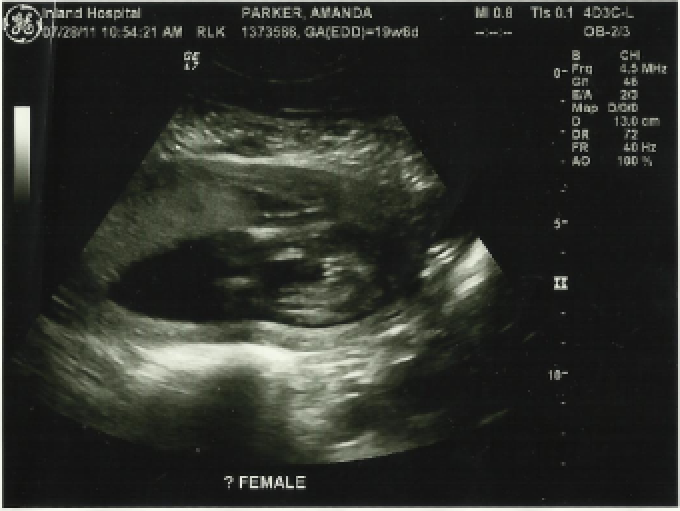

We had our appointment at 10:15 and were on time and ready for the big ultrasound. I drank a Mt. Dew on the way because whenever I drink one the baby is really active. That backfired because it went right through me. We went back in the room and got all situated and the tech tells us the baby is in a horrible position to see in between the legs. We looked around at all the different things for about 10 minutes then she had me go empty my bladder. I was very grateful. I came back in and it moved the baby a little bit but "it" was sitting breach position (feet down, head up) right on it's butt with legs under. We got to see the brain, heart, feet, hands, legs and all the important parts. Still no luck on in between legs. She had me shift on my left side; no luck. Then back onto my back; no luck again. What a shy baby. By this time it'd been about 30 minutes and once again my bladder was getting full. It was funny to see the baby kicking right on my bladder and I could sure feel it. I was afraid if it got too full we'd be done and not get to find out; good one Craig on jinxing it. She had me shift one last time to my right side. Then Jaycee said she had to go potty. Craig says as he walks out, "Maybe the baby is shy and doesn't want a crowd." Right as they left the baby shifted and we got to see! The tech asked if I wanted to know or wait til he came back. TELL ME! You see those 3 lines...IT'S A GIRL! We briefly got to take a look and then back she flipped. Craig came back and asked if "he" was being shy. And I said, "It's not a he." We didn't get to see between the legs again. At the end she said pretty sure a girl but since we couldn't see again we'll try in a couple weeks. But 3 lines is 3 lines. We finished by meeting Dr. Stein. I was very impressed and she was so good with Jaycee and let her put the "goo" on my belly and then use the machine to find the heartbeat. It was cute how much she cared about letting Jaycee help. Jaycee loved it too.

*We couldn't get great pictures because of positioning*

Not the "lack thereof" but "presence thereof" It's really hard to see but the 3 lines indicate girl parts